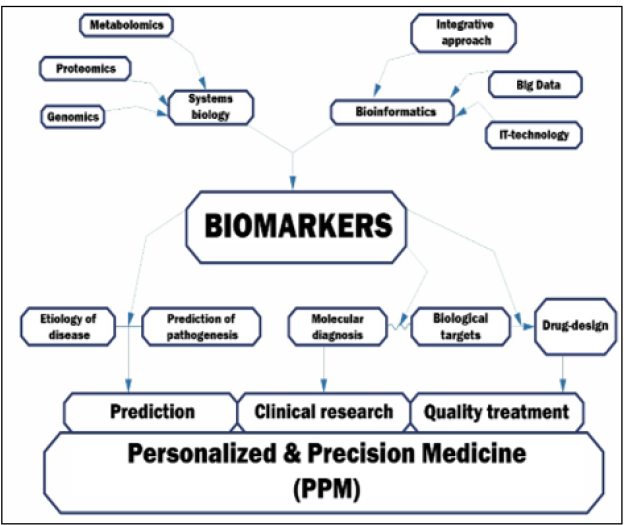

The medicine of the XXI century is Personalized & Precision Medicine (PPM), by protecting and preserving human health throughout the life. Creating and maintaining a high level of public health and thus the wellness is a priority in the health sector. In this regard, an upgraded model of healthcare service, which includes the philosophy, principles and armamentarium of PPM and aimed at identifying the disorder at its early (subclinical) stage, is being created and set up. PPM focuses on predictive and preventive measures that contribute to the development of individualized strategies for managing a healthy lifestyle that stabilize morbidity rates and can help to im-prove the working capacity of the population. Against the background of the development of PPM, there was an explosion and the evolution of the concept of biomarkers (specific bioindicators), whose combinations have been being studied, and their effectiveness and efficacy as working re-sources were being evaluated.

The Grand Challenge of PPM is to forecast, predict, prevent, and treat exceptionally, is rooted in the most recent developments in systems biology, bioinformatics, nanomedicine, and translational medicine. Each of those sciences is a separate niche activity that we hope to see unified to create a new healthcare continuum with great potential future impact on quality-of-life outcomes [1,2]..

Systems biology and OMICS technologies: PPM as being the Grand Challenge to forecast, to predict and to prevent is rooted in a big and a new science generated by the achievements of Systems Biology and Translational Medicine (TriMed), whilst integrating and consolidating platforms of Fundamental Sciences and Newer OMICs Technologies, which are being implemented as The Newest ENTITIES into the daily medical practice to secure Clinical, Subclinical & Predictive healthcare-related manipulations of the next-step generation [3].

Thus, systems biology is helping profoundly to characterize the cooperative networks in cellular and intercellular systems, dynamics, control, and design principles. This information may then be employed to derive new models of practical medicine [1,2].

As a strategic product of translational applications, biomarkers, that gave impulse to the development of the concept of the precise diagnostic and targeted therapy, provide an opportunity to create tools belonging to the fundamentally new generation [13]. Moreover, discovery and clinical application of biomarkers of the principally next-step generations are expected to play a significant role in reshaping life science research and healthcare biopharma and biotech, thereby profoundly influencing the detection, monitoring and curative effects in a broad scope of disorders including cancer in particular (Figure 14A, B).